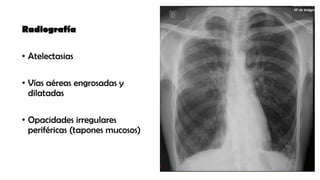

Radiografía

• Atelectasias

• Vías aéreas engrosadas y

dilatadas

• Opacidades irregulares

periféricas (tapones mucosos)

Radiografía • Atelectasias • Víasaéreas engrosadas y dilatadas • Opacidades irregulares periféricas (tapones mucosos)